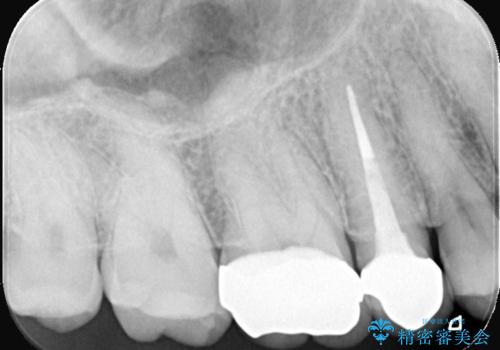

- 長年使用してきた奥歯の古い銀歯のやりかえを主訴にご来院されました。診査の結果、銀歯の下の歯質が薄くなっている部分があり、今後強い力が加わると歯が割れてしまう(破折)リスクが高いと判明しました。このリスクを回避し、歯を長期的に守るため、歯全体をしっかり覆う**セラミッククラウン(被せ物)**による修復を提案。機能的な強度と自然な見た目の両立を目指しました。

治療では、まず古い銀歯を慎重に取り外し、内部の虫歯の有無を確認しました。その後、残っている歯質を保護し、強度を高めるために、適合性に優れたオールセラミッククラウンを作製・装着しました。

強度: 歯全体を覆うため、咬合力による歯への負担を分散させ、破折リスクを大幅に軽減します。